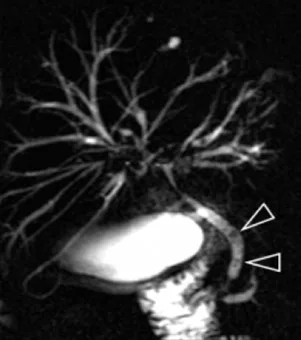

Figure 16. Exemple d’exploration par bili-IRM d’une volumineuse TIPMP de la tête du pancréas (têtes de flèches). Il s’y associe d’autres localisations corporéo-caudales de petite taille, et une augmentation de calibre du canal pancréatique principal

Figure 17. Sur cette bili-IRM demandée à la recherche de lithiases de la voie biliaire principale, découverte fortuite d’ectasies kystiques juxta-centimétriques de canaux secondaires, évoquant des localisations de TIPMP (têtes de flèches)